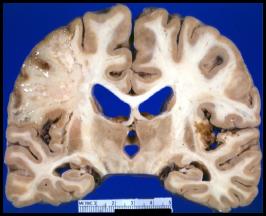

Thrombotic

Here are the corresponding coronal sections through the brain. Do these fit with your observations on the CT scans?